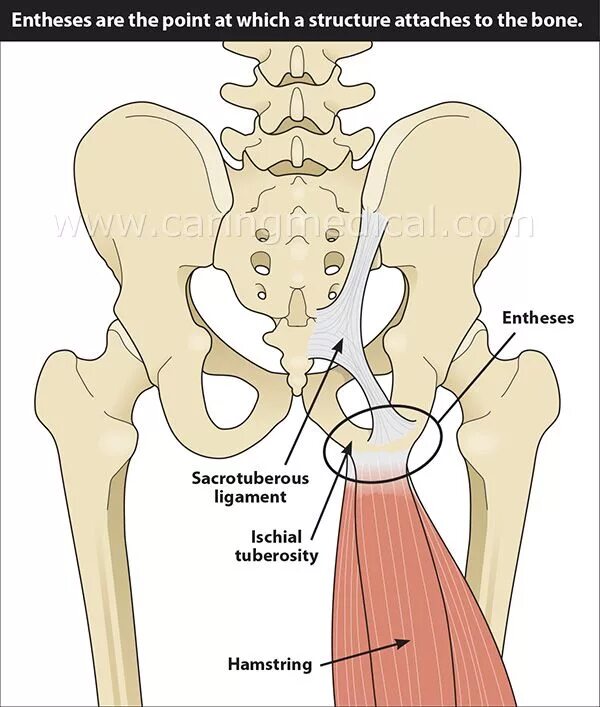

Хамстринг синдром тазобедренного сустава